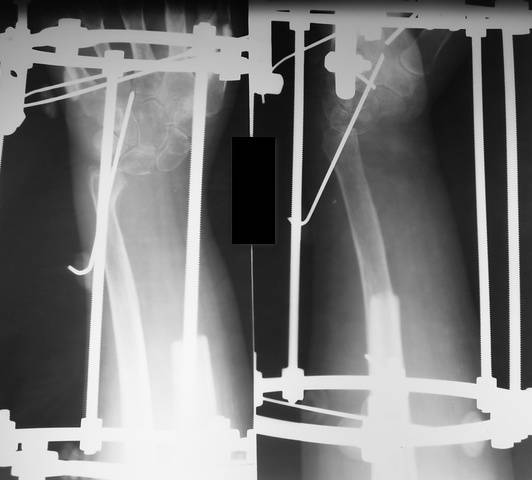

The patient with giant cell tumor of distal radius. |

Больной К., 39 лет : в декабре 2006г. выявлена остеобластокластома лучевой кости. Диагноз подтвержден гистологически. Выполнена краевая резекция с замещением гидроксиапатитом. В сентябре 2007г. рецедив опухоли с бурным ростом. Выполнена резекция н/3 лучевой кости с фиксацией в аппарате. Дефект 11см. На контрольных рентгенограммах (9.01.08) роста опухоли не наблюдается. Вопрос: чем заполнять дефект? The patient 39 year old with giant cell tumor of distal radius. Resection of distal radius is made in September of 2007. Defect forms 11sm. What about reconstraction ?

Добавленные снимки

P1300064-1.jpg